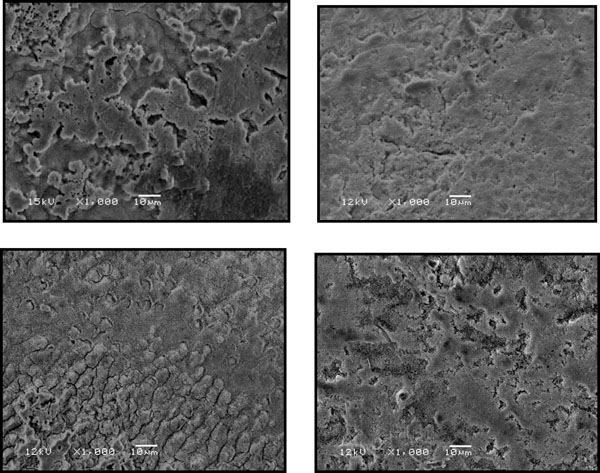

Fig. (2).

The effect of 20 sec etching on the enamel of 2 permanent premolars as observed by SEM at x1000 magnification. Note on the left the removal of inter-prismatic layer (type 1) and on the right the removal of the intra-prismatic layer (type 2).

Fig. (2) shows the effect of 20 seconds etching on 2 permanent premolars used as controls. On the left the etching caused removal of interprismatic area (type 1), and on the right the etching caused microporous surface due to removal of the prisms (type 2).